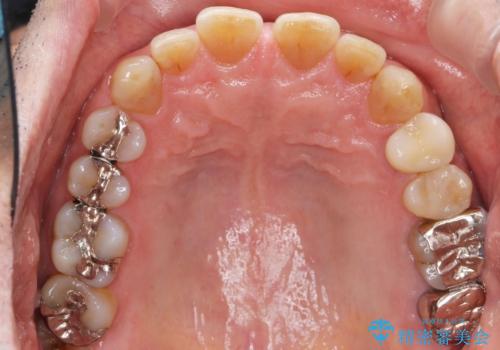

精査したところ、奥歯(左上67)の根尖部に位置した歯茎に瘻孔(膿の出口)ができており、CTを撮影し確認すると奥歯2本(左上67)の根尖病変は大きくつながっていました。

銀座しらゆり歯科の林院長による精密根管治療を受けて頂いたのち、メタルボンドクラウンによる補綴を行いました。